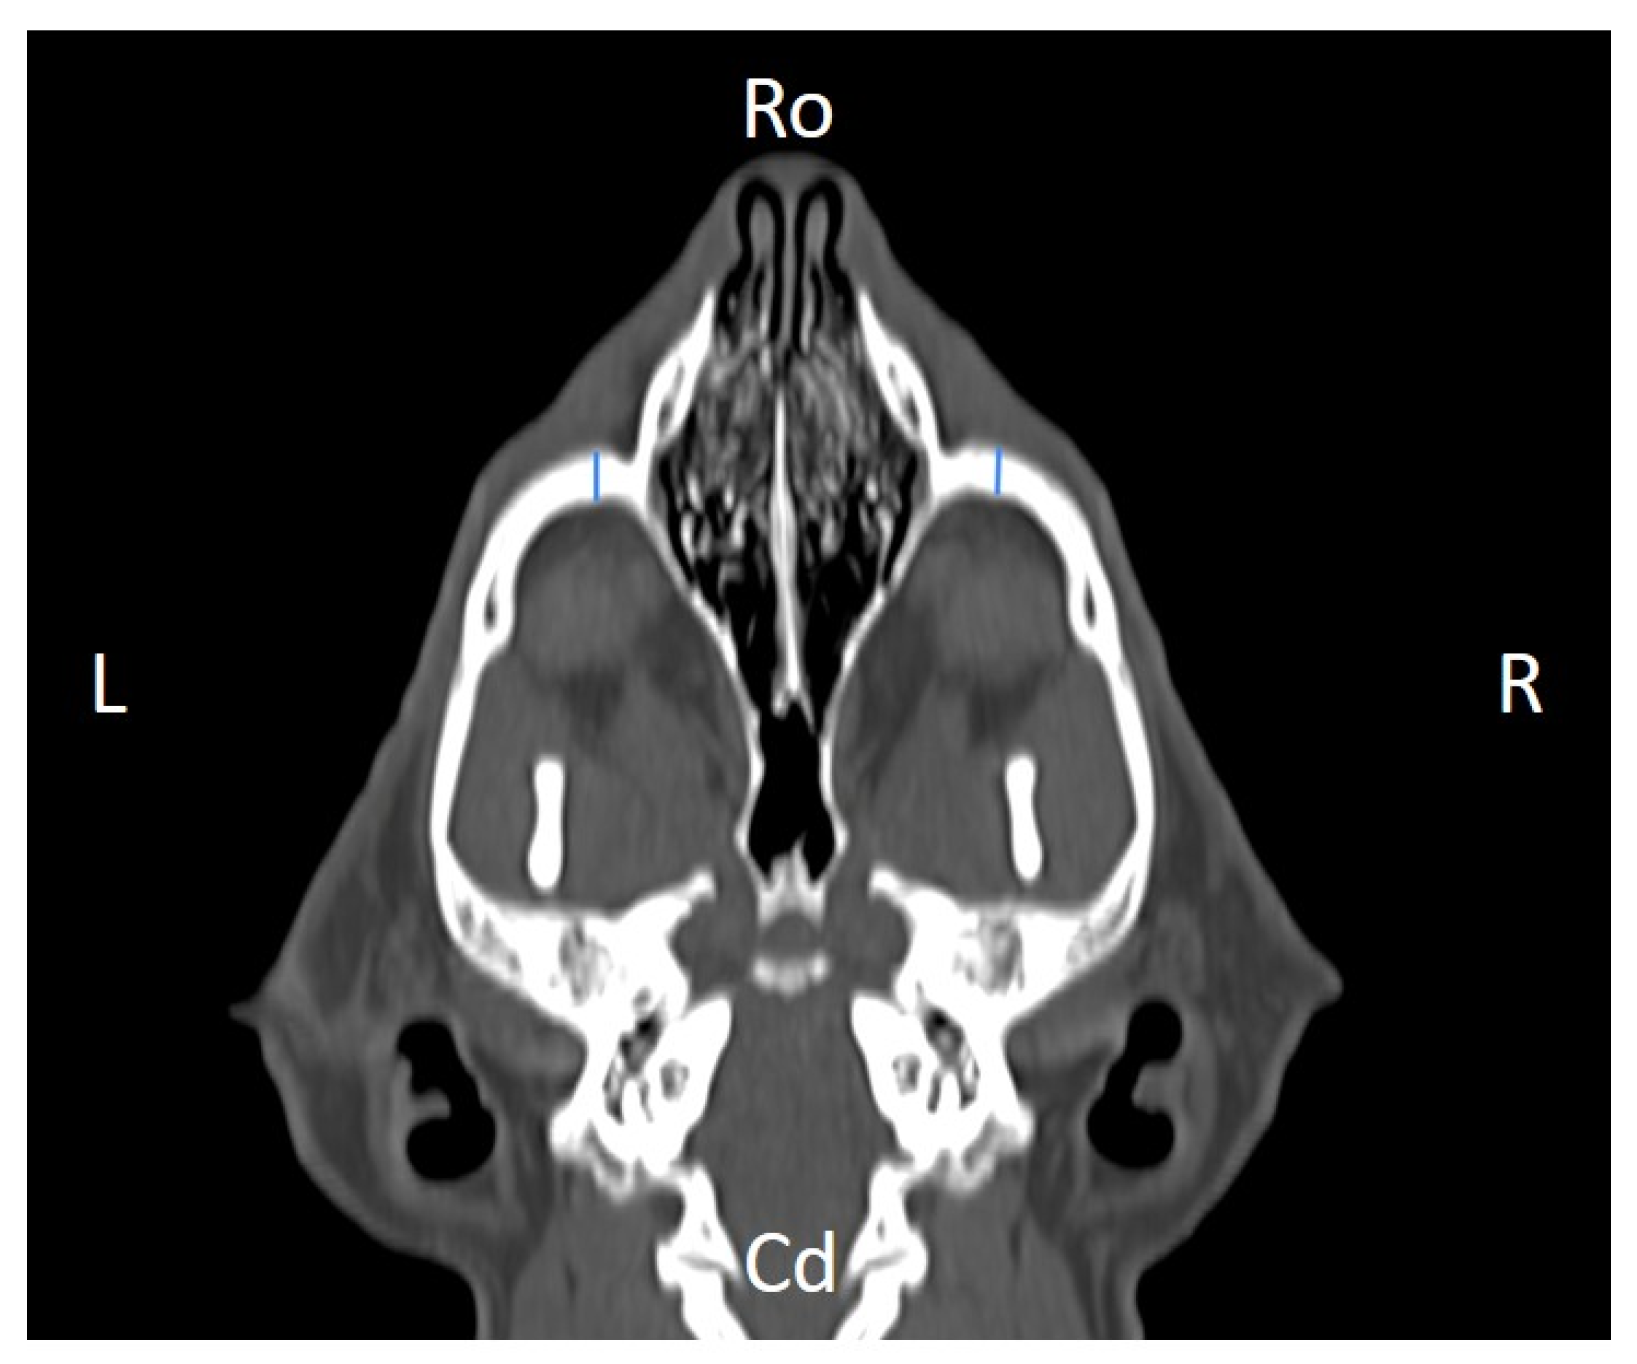

Linear morphometric parameters (Table 1) were obtained directly from CT images using HorosTM v3.3.6.dmg DICOM software with bone filters. Prior to measurement, all images were calibrated from pixels to millimeters. A preliminary study and prior training were conducted, to establish anatomical landmarks that would allow for the repeatability of the measurement methodology by J.F.R., A.R.S., S.A.-P. Recorded variables included infraorbital foramen major axis (Figure 2), minor axis (Figure 3) and length (Figure 4), distance between infraorbital foramina (DIF) (Figure 5), orbital height and width (Figure 6 and Figure 7), zygomatic arch width (Figure 8), skull width and length (Figure 9). Ratios were calculated to normalize for skull size. As preliminary results revealed adequate repeatability of measurements, and in order to reduce the analysis margin of error, two measurements of each studied parameter were performed. The measurements were performed by the same operator (to reduce interpersonal errors), and each measurement of each parameter was performed at different times, in order to reduce intrapersonal errors. Then, the arithmetic mean of the measurements was calculated.

Figure 4. Infraorbital canal length (ICL) measured at the left and right sides, on a dorsal CT image (blue lines). Cd, caudal, L, left, R, right, Ro, rostral.